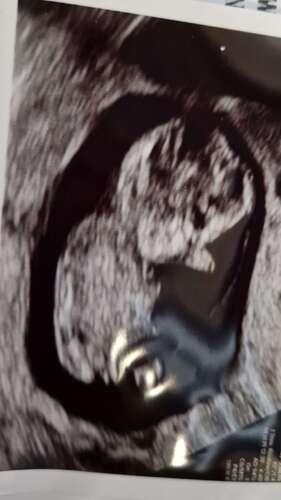

Iemand een idee? Termijn 12,2😊

Volgensmij staat de nub in een hoek, en dat betekend een jongen😊